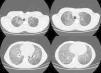

Upon admission to the pulmonology unit, the patient had dyspnea grade I–II. Physical examination revealed good coloration of the skin and mucous membranes, and finger clubbing. Baseline O2 saturation was 93% and good vesicular breath sounds were perceived upon auscultation, with no added noises. Spirometry indicated FEV1: 44%, FVC: 47%, FEV1/FVC: 79, MMEF: 29%, although patient cooperation was incomplete. The chest X-ray showed an extensive bilateral alveolointerstitial pattern with multilobar involvement. The examination was completed during hospitalization with high-resolution computed tomography (HRCT), in which marked alteration of the lung parenchyma was observed, with large ground-glass fields in all lobes, but predominantly basal. There was overlapping septal thickening, forming a crazy-paving pattern (Fig. 1). Furthermore, honeycombing areas were visible in the subpleural lung parenchyma at the level of both upper lobes, although predominantly in the right side.

The most common HRCT radiological findings in LP4,5 are the presence of condensation with low attenuation coefficient (between −75 and −35 UH) that is very specific and prevalent in endogenous LP,1 ground-glass opacities, crazy-paving pattern, and presence of centrilobular opacities. In addition, lung involvement is mainly basal.4

The crazy-paving pattern was initially described in alveolar proteinosis, although it was later shown to appear in several processes,4 including sarcoidosis, non-specific interstitial pneumonia, organizing pneumonia (both cryptogenic organizing pneumonia and bronchiolitis obliterans organizing pneumonia) pulmonary infections (mainly viral and mycoplasma), malignancies such as bronchoalveolar carcinoma, hemorrhage, pulmonary edema and LP.